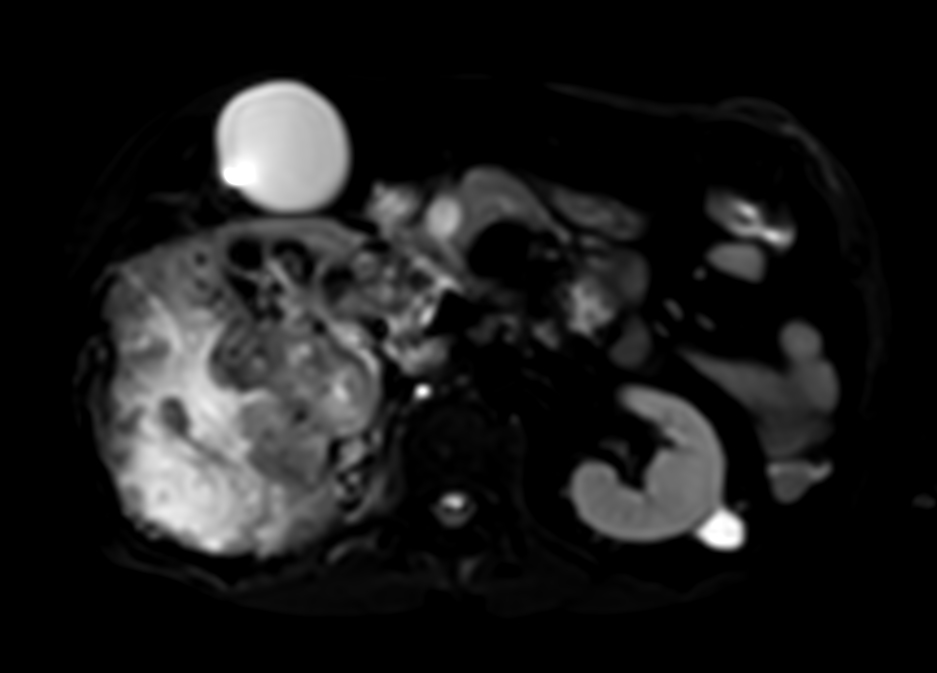

Patient with kidney tumor. ExamCard includes Compressed SENSE to shorten the breath hold time, VitalEye for touchless respiratory sensing, mDIXON XD FFE to acquire up to four image types in one single scan, DWIBS to achieve high contrast between background and lesions and bTRANCE for non-contrast time-resolved imaging.

bTFE - VitalEye Compressed SENSE

T2w SPAIR - VitalEye Compressed SENSE